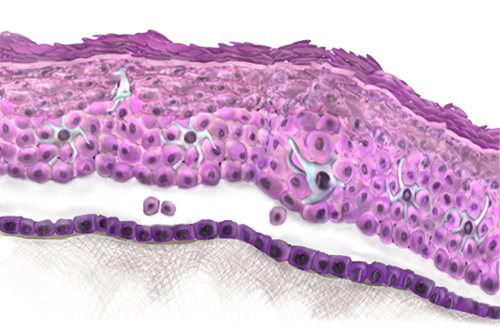

INTERACTIVE 3D MODEL OF THE SKIN

For more information on how to navigate the model, click on the question mark icon on the bottom right corner of the viewing screen.

EPITHELIUM OF THE SKIN

The epidermis of the skin is an epithelial tissue layer that covers the entire body, forming a barrier between the human body and the environment. Skin must be tough and therefore an epithelium with many layers that can be eroded and abraded without damaging the basement membrane is ideal. As such, skin consists of stratified squamous epithelium. For even tougher external surfaces a thick layer of keratin is produced on top of the squamous epithelium. Occasionally epithelium can change from one type to another (metaplasia) in response to injury. As it is a tough epithelium many tissues alter their surface to bear squamous epithelium.

FIRST LAYER OF THE EPIDERMIS: THE BASAL LAYER

The deepest or basal epidermal layer is the germinal or proliferative cell layer.

This layer comprises of a single row of cells resting on a basal lamina, which is strongly adherent to the underlying dermis. The basal layer contains the replicative pool of germ cells. These cells give rise to daughter cells that continue to mature through the height of the epithelium.

This can be seen morphologically as basal cells have relatively little cytoplasm and appear much darker whereas cells in the upper layer have much more cytoplasm and appear much lighter.

SECOND LAYER OF THE EPIDERMIS: THE PRICKLE CELL LAYER

The prickle cell layer represents the first area of maturation above the basal cells.

This layer is about five cells thick and is so named because the cells appear to have spines or prickles projecting from their surface. These are desmosomes on fine spike-like cytoplasmic processes; they interdigitate and attach to neighbouring cells.

THIRD LAYER OF THE EPIDERMIS: THE GRANULAR LAYER

Transformation of the spinous cells into the cells of the third layer, the granular layer, is characterised by accumulation of numerous dense cytoplasmic granules containing proteins that eventually go on to form keratin. At the same time the nucleus and organelles break down and their ultimate destruction results in cells filled only with keratin. The cells of the granular layer have the distinction of being programmed to destroy their nuclei and organelles, yet at the same time to synthesize keratin and lamellar bodies.

The contents of the lamellar granules in the granular cells are discharged into the extracellular space and provide a lipid layer between the succeeding cell layers. This is effective in establishing permeability for the skin.

FOURTH LAYER OF THE EPIDERMIS: STRATUM LUCIDUM

In thick skin a narrow fourth layer, the stratum lucidum, is sometimes observed above the granular layer. It consists of flattened, dead cells with abundant keratin proteins and it is observed as a thin, undulating line of poor staining intensity.

FIFTH LAYER OF THE EPIDERMIS: THE KERATIN LAYER

The fifth and most superficial layer is the keratin layer, which consists of dead, anucleate squamous cells containing keratin. it is especially thick (more than 1 mm) on the soles of the feet and quite thin (about 0.1 mm) over much of the body surface. Thus, the number of individual cell layers making up the fifth layer can range from about 10 to a few hundred. These plates of keratin, which are also referred to as the horny layer of cornified cells, are constantly shed from the surface and replaced by new cells arising from the deeper layers. Normally the transit time from a stem cell to desquamation is about 1 month.

In the image on the right the structures surrounding the model can be viewed, as well as the situation of the epithelium in relation tot them.